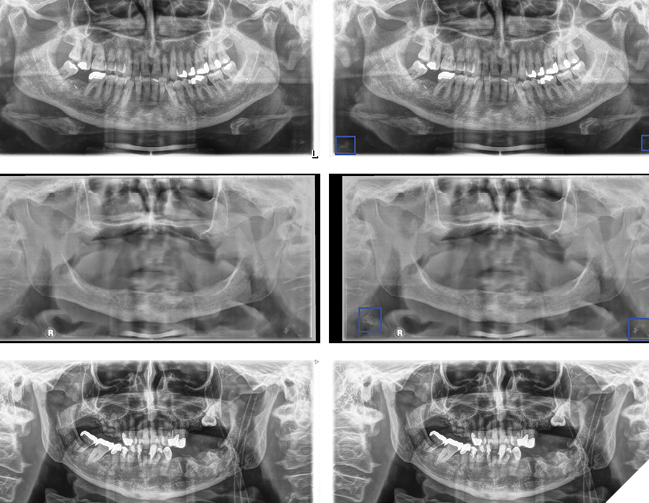

Dentistry has always been about more than just teeth, but AI is taking it to a whole new level. Routine dental visits, often more frequent than medical check-ups, offer a unique opportunity to screen for systemic diseases (Fig. 2). Panoramic radiograph (PR), a standard imaging modality for dental diagnostics, captures a detailed view of the jaw, teeth, and surrounding structures, making it ideal for spotting abnormalities beyond cavities and crowns. Yet, dentists often lack specialized training to recognize signs of conditions like carotid artery calcification (CAC) or osteoporosis, leading to missed opportunities. AI steps in where human expertise falls short, automating the detection of these “outlier” pathologies with remarkable accuracy. By doing so, it empowers dentists to act as first responders in healthcare, flagging risks and referring patients to specialists before symptoms escalate.

Fig. 2